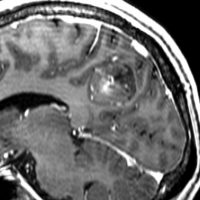

7才の時に音読でつかえるようになり,眼で何かを追っているような欠伸発作(左側頭葉てんかん)を繰り返すようになり,強直間代発作を生じて腫瘍が発見されました。下側頭回底面の皮質に発生した境界明瞭な腫瘍であり,周囲に脳浮腫を伴っています。T2強調画像で線維成分の多い硬い部分は低信号に,軟らかい部分はやや高信号となり,ガドリニウムでheterogenousに増強されます。グレード1の神経節膠腫としては非典型的な画像所見で術前診断は難しいもので,PXA pleomorphic xanthoastrocytoma も疑いました。もちろん治療としては開頭手術での全摘出です。術後に発作は消失しています。

構成要素はGFAP陽性の膠細胞が多く認められます。神経細胞様形態の細胞 ganglion cellではNeuN(+), CGA (+) synaptophisin (++), neurofilament (+)です。大型で腫大した核を有して核内封入体構造を有する好酸性もしくは淡明な細胞質を有する細胞が増殖してPXAを考えさせる部分像もありました。granular bodyも認められて,右の写真のように膠原線維の増生が目立つ部分もあります。これは表面の非常に硬い線維性の腫瘍部分です。MIB-1 indexは4%とやや高い値です。BRAF v600Eの変異が認められました。